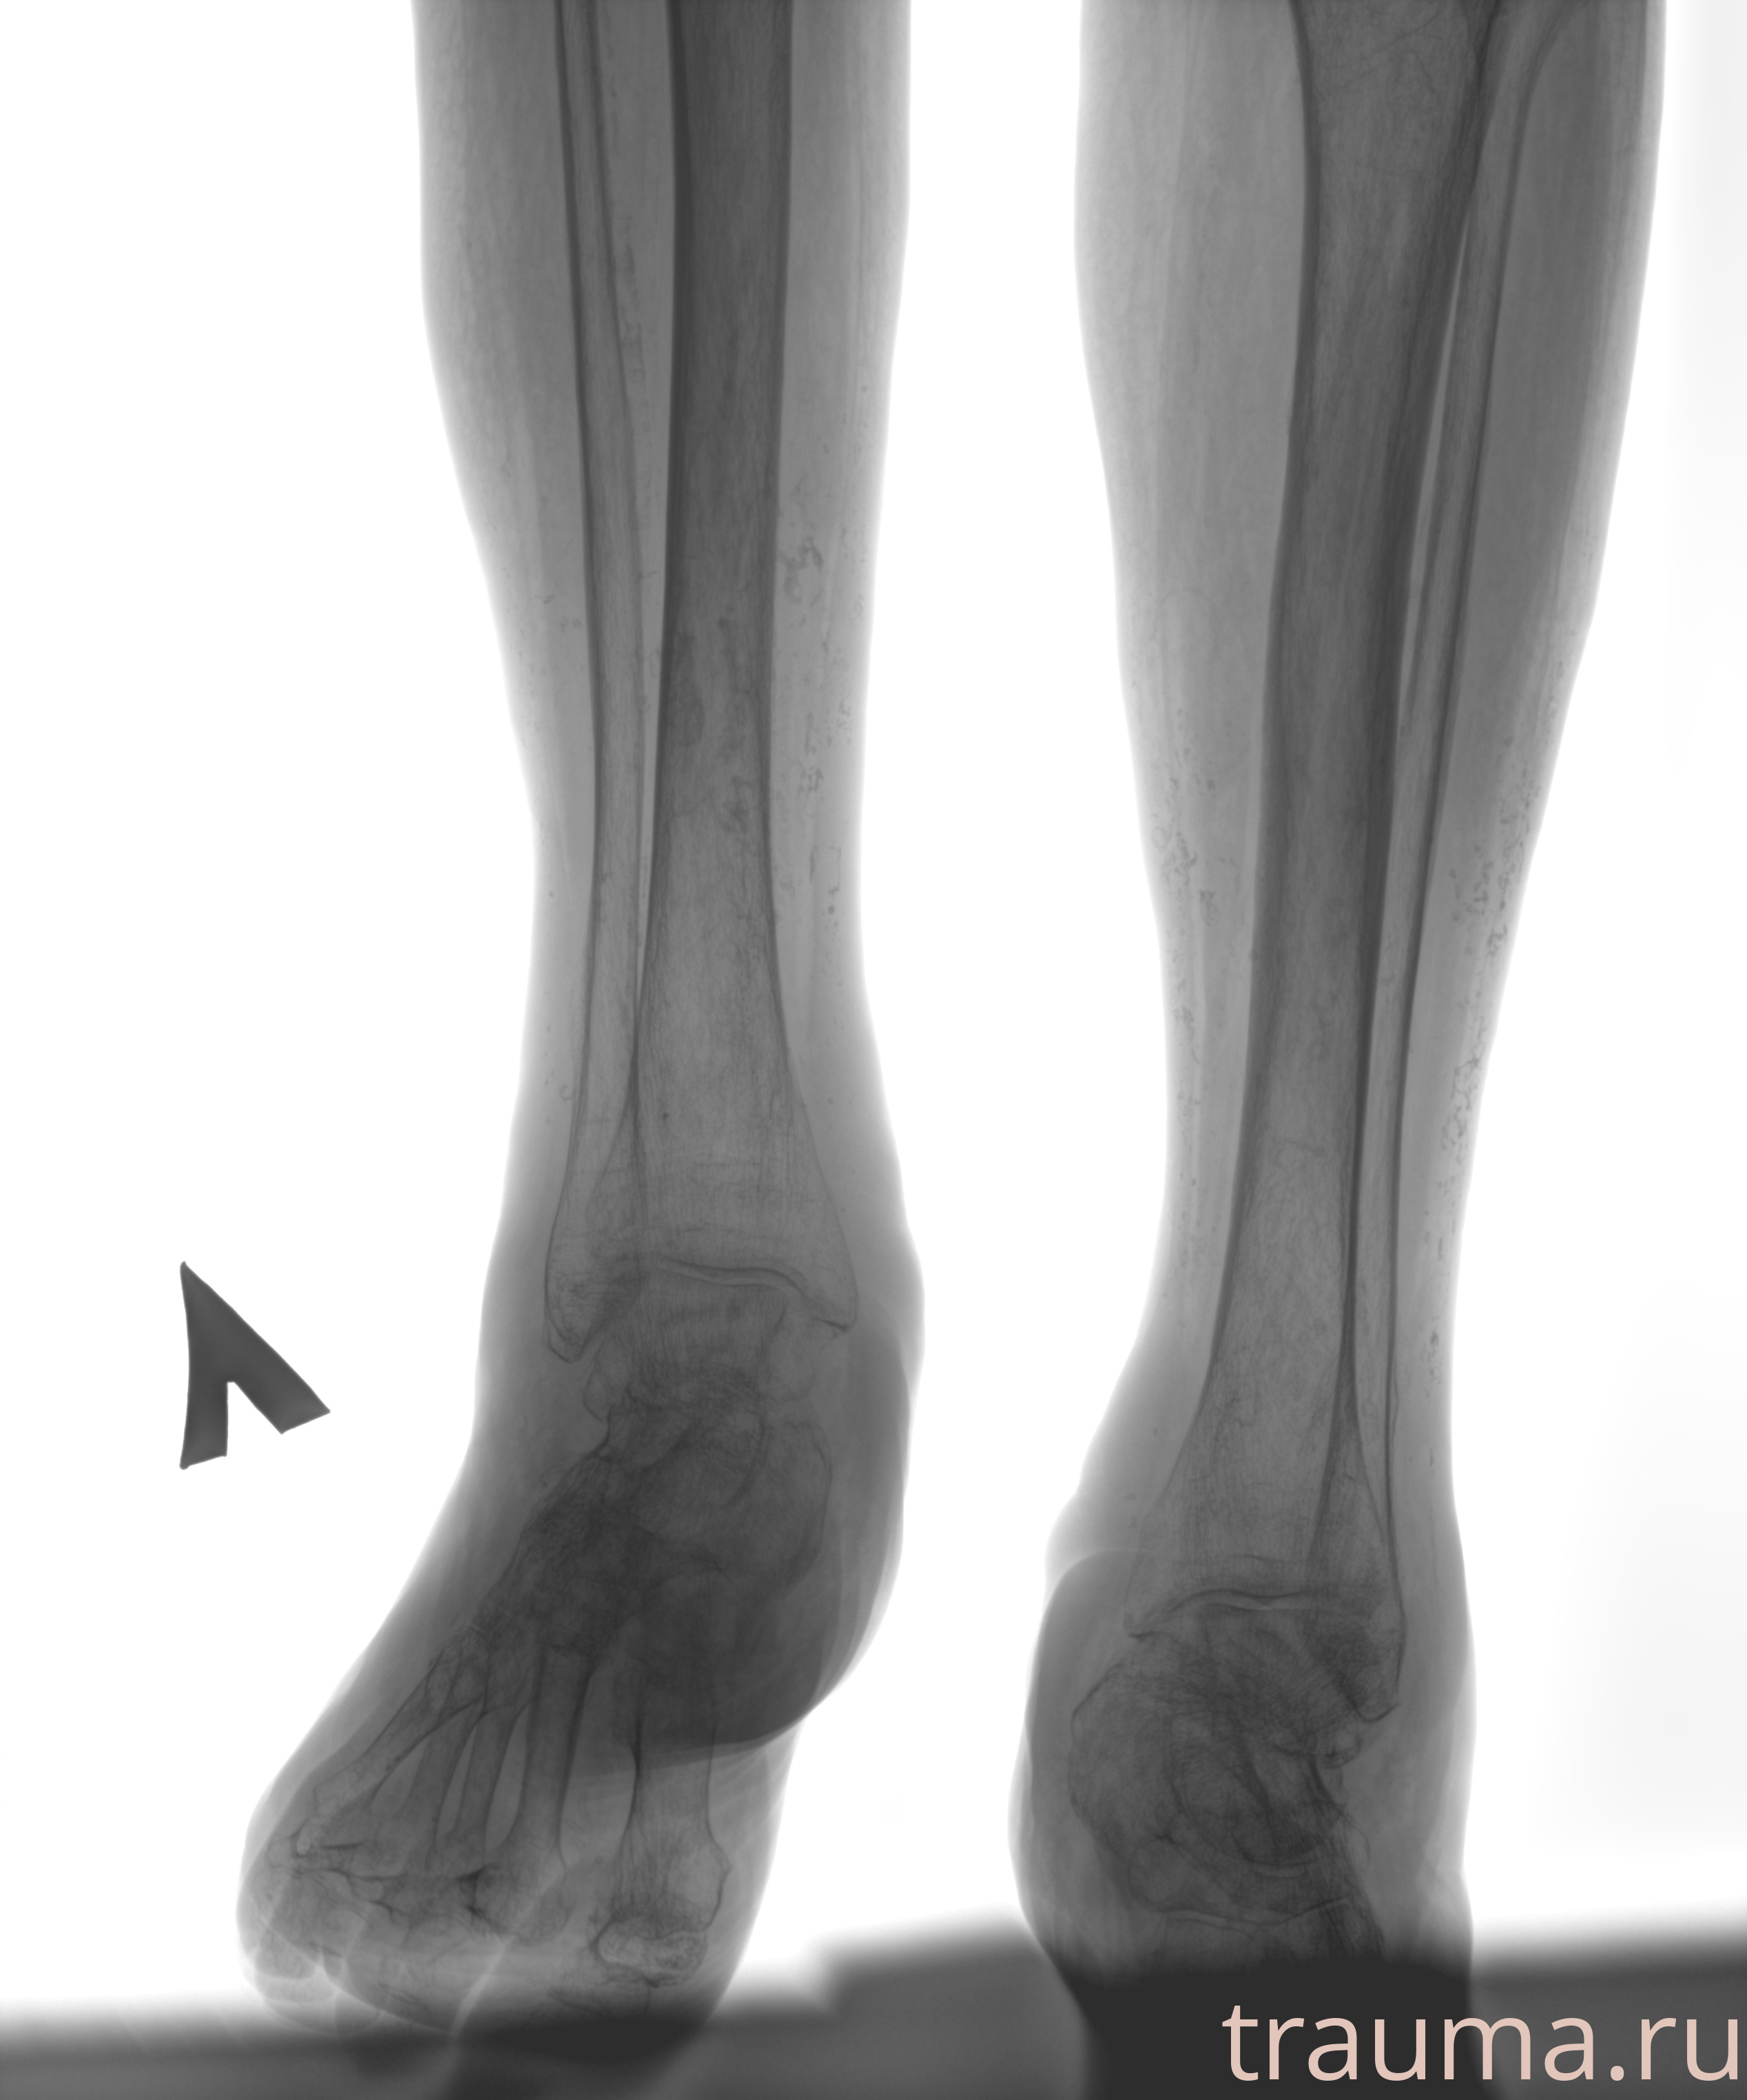

Рентгенограммы

Рентген на дому: по вашему адресу приезжает врач-рентгенолог, травматолог-ортопед с мобильным рентгеновским аппаратом, проводит диагностику травмы или заболевания, делает необходимые рентгенограммы, дает рекомендации по дальнейшему лечению. Получить качественные снимки в домашних условиях возможно благодаря уникальной методике, разработанной МосРентген Центром для института  Склифосовского